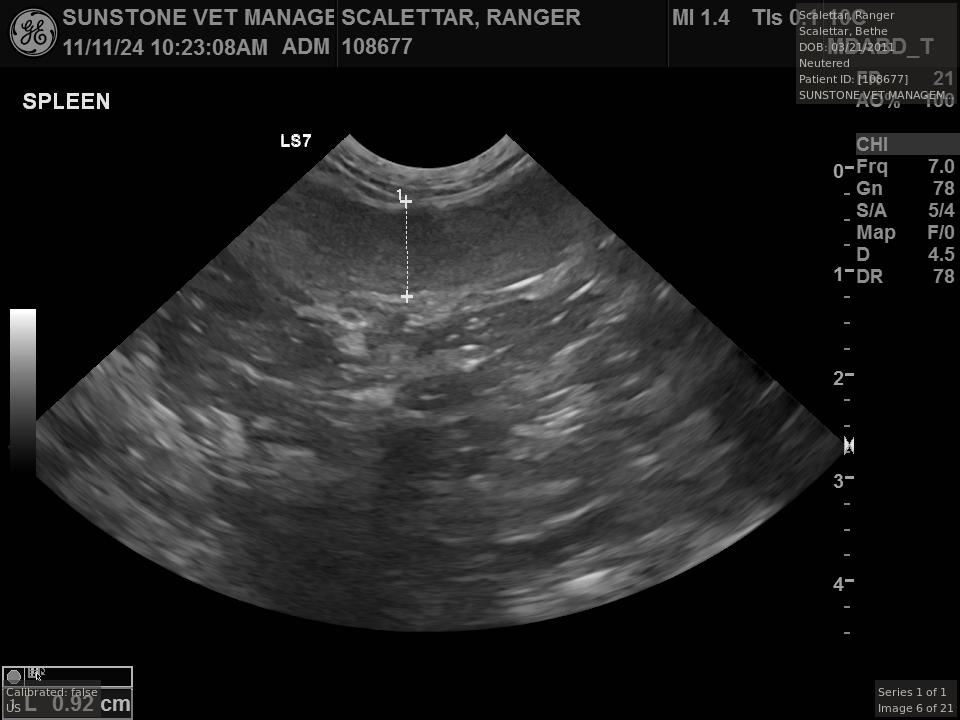

The veterinarian generated a series of images showing different organs and substructures by

changing the position and orientation of the ultrasound transducer. The images were collected

in a defined order, which is repeated from patient to patient, ensuring that nothing is missed. In

Ranger's case, the sonographer collected about twenty images during an examination that

lasted about fifteen minutes.

The sonographer stated that Ranger's ultrasound images were largely normal for an older cat. In particular, they show changes in the kidneys that are commonly noted in geriatric cats and that reflect a risk for the development of chronic kidney disease. However, the images did not show any significant abnormalities in Ranger's stomach, intestines, and associated lymph nodes. Nonetheless, the results did not rule out recurrence of Ranger's small cell lymphoma.